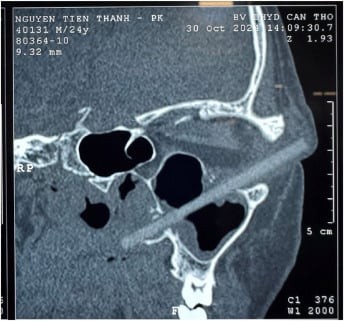

Həkimlər müayinə zamanı kişinin görmə qabiliyyətində problem olmadığını və göz almasının zərər görmədiyini müəyyən ediblər. Lakin kompüter tomoqrafiyası nəticəsində göz yuvasında 9 santimetr uzunluğunda yad cisim aşkar edilib. Məlum olub ki, bu, taxta yemək çubuğudur. Çubuq yumşaq toxumalardan keçərək göz yuvasının arxasına, üst çənə boşluğunun üst divarına və burunun yan divarına ziyan vurub.